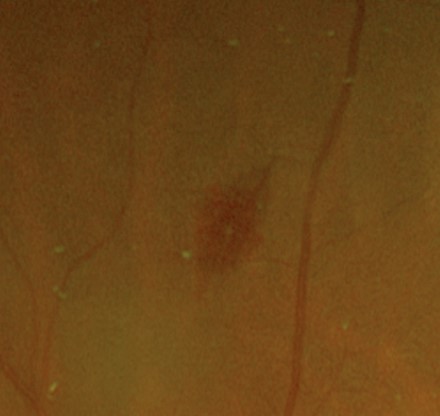

A Roth spot is a flame haemorrhage with a characteristic white centre. These haemorrhages are associated with a variety of systemic disease, most notably with bacterial endocarditis. Other associated conditions include leukemia, anaemia, hypertensive retinopathy, pre-eclampsia, diabetic retinopathy, human immunodificiency virus (HIV), pre-eclampsia, shaken baby syndrome and anoxia.

Roth spots are the result of retinal capillary rupture and intraretinal hemorrhage. The white centre of the lesion is composed of fibrin that has formed a fibrin-platelet "plug" at the site of capillary rupture.

Retinal photo and red-free image (left inferior retina)